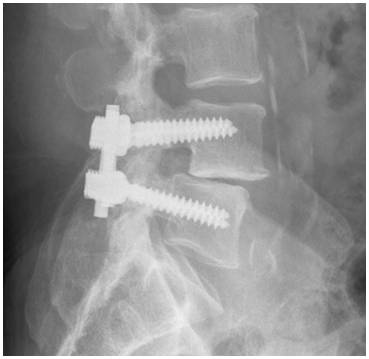

PLF

In this X-ray of posterolateral lumbar fusion (PLF), a rod and screws have been used to prevent motion at the spinal segments being fused.